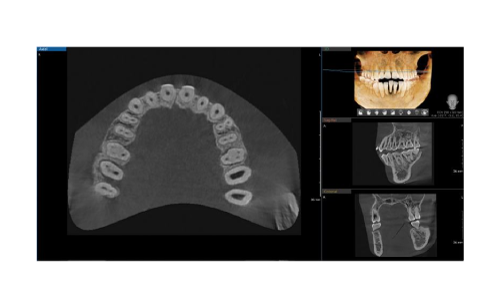

INTEGRAL FOV FOR 3D IMAGE

The Vatech A9 offers precise, high-quality panoramic images, enhancing diagnostic accuracy and treatment planning. Its innovative FOV provides a wider view of the dentition, reducing the risk of cutting out images of teeth. The 8×8 images enable comprehensive diagnoses and treatment planning, including complex implant surgeries and TMJ diagnoses, in a single scan.

INTEGRAL FOV FOR 3D IMAGE

The Vatech A9 offers precise, high-quality panoramic images, enhancing diagnostic accuracy and treatment planning. Its innovative FOV provides a wider view of the dentition, reducing the risk of cutting out images of teeth. The 8×8 images enable comprehensive diagnoses and treatment planning, including complex implant surgeries and TMJ diagnoses, in a single scan.